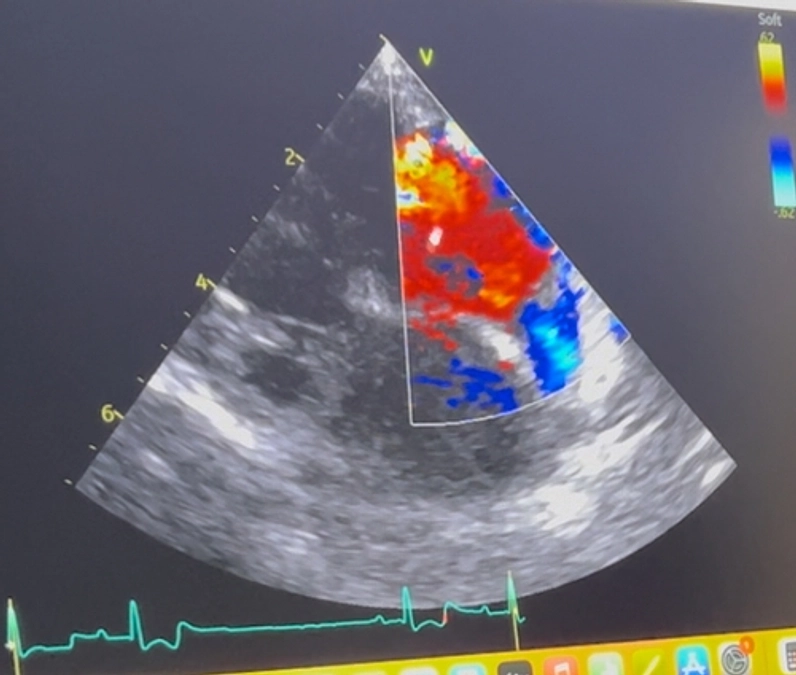

僧帽弁閉鎖不全症の手術を受けることができました。

三尖弁閉鎖不全症、尿管結石、

気管虚脱、腎臓の腫瘍